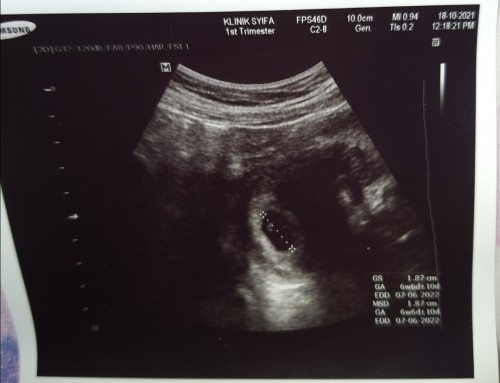

Kiraan sy 6w5d tapi 1st scan showing 6w6d.. sy scan awal sbb cramping yg kuat mlm smlm.. thank god ad keluar pd screen scan.. walau tiada bleeding, rasa perubahan mual.. god willing, sy akan update lg.. doakan sy #1stbaby